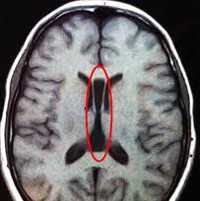

МРТ головного мозга. Арахноидальная киста полюса левой височной доли. Цветовая обработка.

Кисты головного мозга - это аномалии его развития. При МРТ в СПб мы видим задачу в дифференциальной диагностике с кистозными формами опухолей. При МРТ головного мозга некоторые виды кист, особенно дермоидные, сами напоминают опухоль.

Арахноидальные кисты представляют собой скопление ликвора между листками расщепленной паутинной оболочки. Арахноидальная киста обычно не сопровождается другими мальформациями. Незначительная часть арахноидальных кист имеет приобретенное происхождение - следствие лептоменингита, операции или кровоизлияния. Частота составляет около 1% от внутричерепных образований. Соотношение полов М:Ж, как 4:1. Типичная локализация - средняя черепная ямка (в области Сильвиевой борозды 50%), межполушарная щель, мосто-мозжечковый угол (11%), за скатом или на уровне четверохолмия (10%), в области червя мозжечка (9%), реже в области межножковой и предмостовой цистерн (3%), а также супраселлярной и хиазмальной цистерн. В зависимости от размера предложено делить кисты на 3 типа (Galassi, 2006), что однако, не имеет практического значения. Ретроцеребеллярная арахноидальная киста довольно часто встречаются за мозжечком и отличима от mega cisterna только по неизменённой задней черепной ямке. При МРТ головного мозга содержимое кисты чисто ликворное, стенки гладкие, чётко очерченные, внутри кисты могут быть перегородки. Мелкие арахноидальные кисты очень трудно увидеть при МРТ головного мозга. Меняя ширину окна и его уровень на Т1-зависимых МРТ изображениях можно заметить, что киста чуть светлее ликвора. Дифференциальная диагностика с эпидермальными кистами лучше осуществляется с помощью МРТ последовательности FLAIR. На них при МРТ головного мозга эпидермальные кисты становятся яркими, в отличие от гипоинтенсивных арахноидальных. Вероятно, вариантом арахноидальной кисты является нейроэпителиальная киста, которая при МРТ головного мозга имеет типичное расположение в области хориоидальной щели.